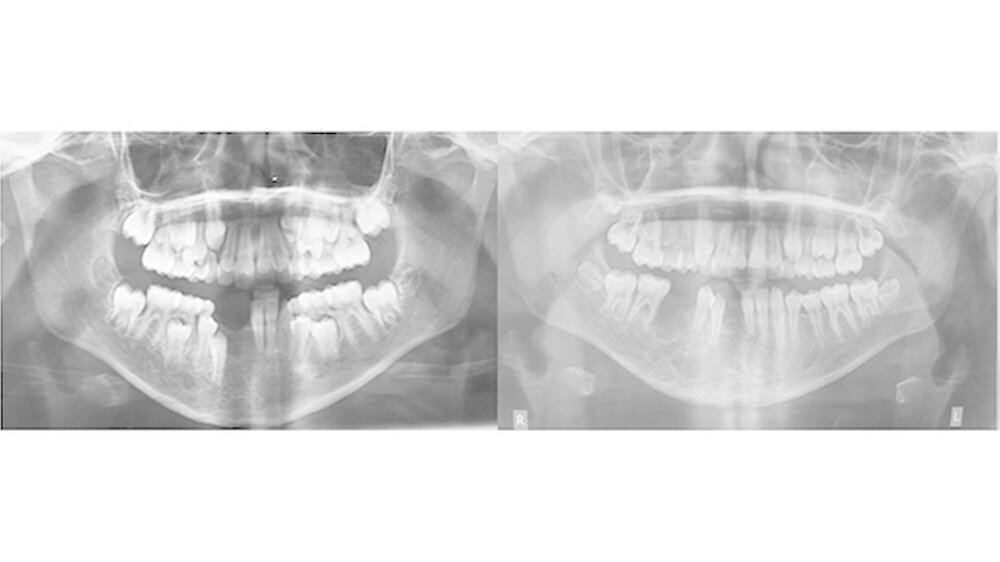

Ausgangssituation:Im Alter von 9 Jahren wurde die Patientin aufgrund gelockerter Zähne im vierten Quadranten des bleibenden Gebisses mit rezidivierenden Zahnfleischblutungen vorstellig. Die anschließend durchgeführte Diagnostik mit Probengewinnung bestätigte den Verdacht einer arteriovenösen Malformation.

Therapie und Verlauf:Trotz mehrfach primär durchgeführter Embolisationen mittels Polyvinylalkohol und Äthylen-Vinyl-Alkohol Copolymer (Onyx®) (Abb. 1) kam es zu einer Größenprogredienz des bestehenden Befundes mit Beteiligung der äußeren Haut submental (Abb. 2).

Auf Basis einer präoperativen computerassistierten Planung wurde eine Unterkieferteilresektion mit primärer Rekonstruktion mittels mikrovaskulärem Fibulatransplantat durchgeführt (Abb. 3). Die Patientin ist seitdem beschwerdefrei und es konnte keine weitere Progredienz des vorbestehenden Befundes beobachtet werden (Abb. 4).